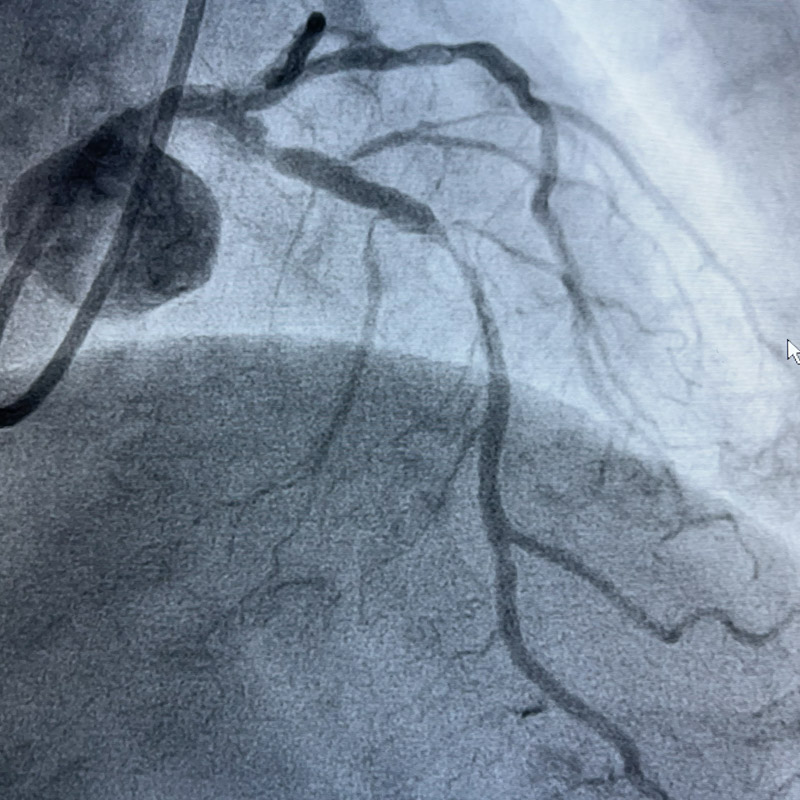

75歲的高齡患者莫阿姨今年九月初曾因突發胸痛在外院做了支架置入術,11月28日,又出現了胸痛癥狀,遂來到了柳州市人民醫院。經復查患者冠脈造影提示前降支嚴重鈣化、迂曲,前降支近段原支架嚴重膨脹不全,殘余狹窄明顯,如果不及時處理,會出現支架內血栓、支架內再狹窄等潛在風險,嚴重威脅患者生命!

術中,心血管內科介入團隊將Shockwave C2 IVL 3.0*12mm 震波球囊置入前降支病變處,以4-6atm進行擴張后觸發8次10秒沖擊波,實施鈣化斑塊碎裂術,術后支架膨脹不全處明顯擴張,并順利于前降支近中段植入1枚支架。復查IVUS可見鈣化斑塊碎裂,支架貼壁和膨脹良好,血管擴張成形滿意,術后患者胸痛癥狀明顯好轉。

▲ 震波前、后造影對比圖